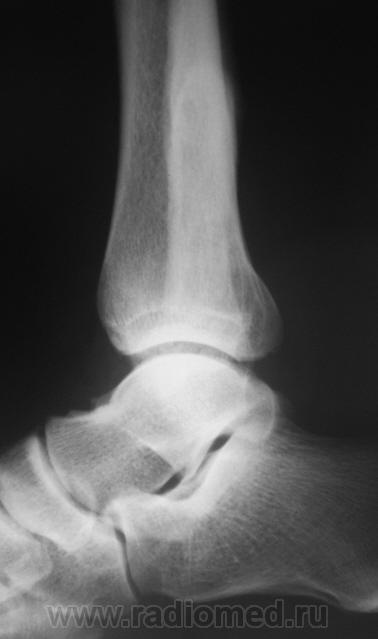

Пациент, в течение последних 2-х лет, жалуется на боли в нижней трети голени. Сегодня, хирургом, пациентка направлена на рентгенографию костей дистальной трети голени и голеностопного сустава. Что посоветуете уважаемые коллеги?

Неоартроз между экзостозами? А что это за вздутие м/б кости на уровне неоартроза и пятнистость наружного кортикала? Следствие хронической воспалительной реакции?

Соглашусь с Вами по поводу экзостозов.

Какая-то непонятная структура костной ткани в области задней лодыжки.

Некоторая порозность, вероятно, нарушение трофики

В области внутренней лодыжки тоже пороз.